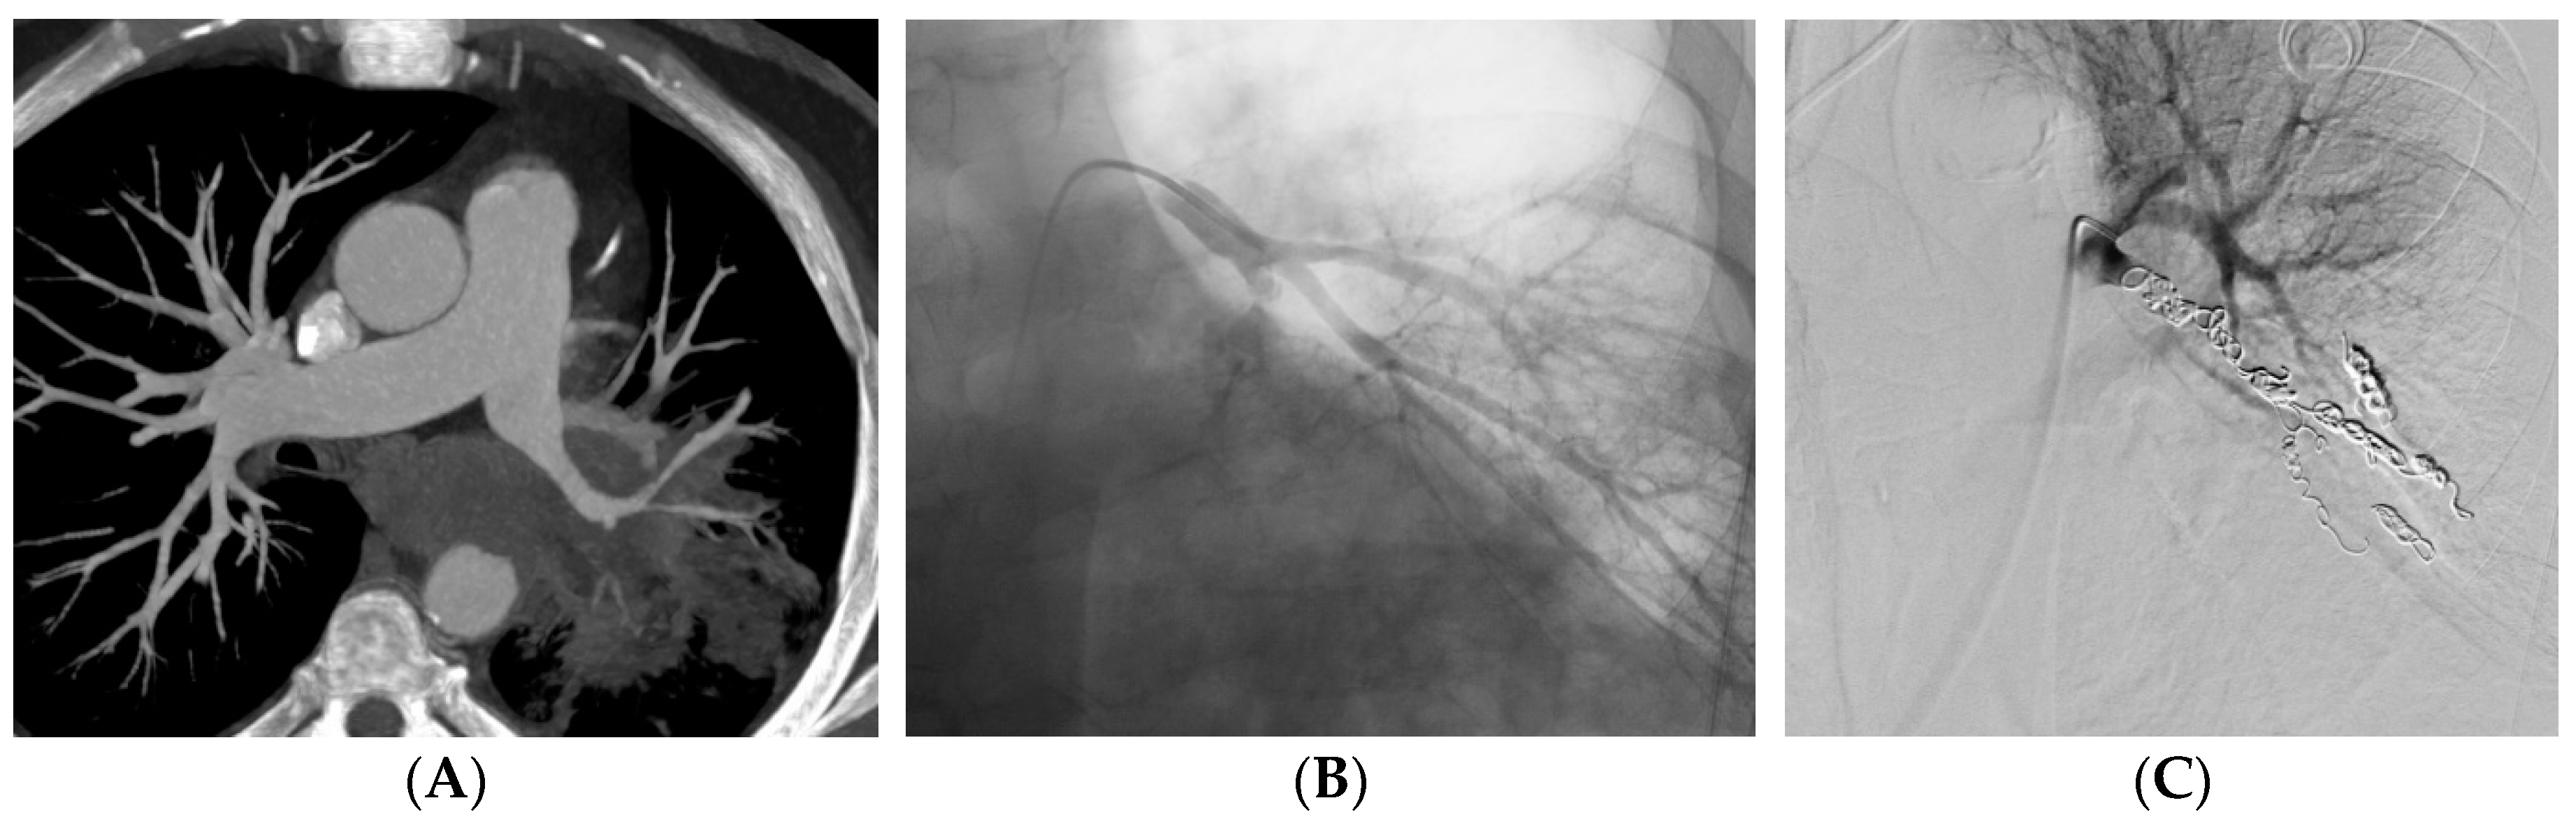

Figure 2. A 62-year-old man with epidermoid carcinoma. He was referred to the RCIU for massive hemoptysis. (A) CT before embolization shows irregularity of the left common basal pulmonary artery. (B) Basal pulmonary artery angiogram confirms the irregularity. (C) Embolization with coils of the left common basal artery angiogram shows complete occlusion.

Embolization was carried out at the lobar level in 34 (37%) patients and more proximally in 31 (34%) patients (Table 2). The material used for the embolization was coils in 35 (39%) patients (Figure 2), a stent-graft in 29 (32%) patients (Figure 3), acrylic glue in 13 (14%) patients (Figure 4), a vascular plug in 12 (13%) patients and gelatin sponge in 1 (2%) patient. In 2 patients, the embolization material was not mentioned in the radiological report. Among the 90 patients, 15 patients had a secondary embolization device used including vascular plugs in 8 cases, metallic coils in 4 cases and gelatin sponge in 2 cases. Mean fluoroscopy time was 25.1 ± 12.5 minutes (median 21.0; min-max 7.0-51.0) and mean radiation dose was 74,277.0 ± 112,855.8 mGy.cm (median 42,548.0; min-max 2,109.0-567,047.0).